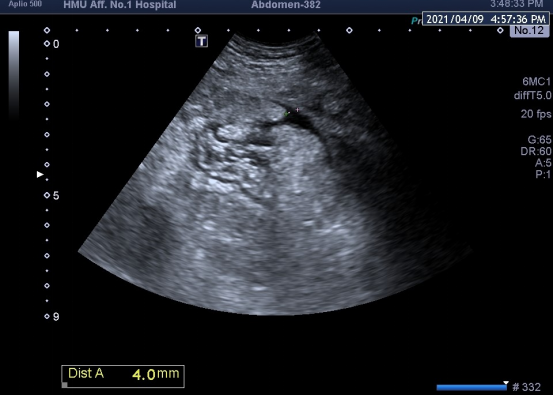

3月31日哈医大一院消化内科史立君教授、徐丹教授联合腹部超声室杨秀华教授成功为一名疑难危重患者采取精准介入手段对其微量腹腔积液进行诊治,在超声引导下通过仅宽约4mm(风险极高)的进针路径为患者实施腹腔积液穿刺置管引流,成功引流液体减轻患者症状,并为临床明确诊断进一步提供可靠证据,助力患者病情好转。

汤某,男,30岁,腹胀1月余,经反复治疗未见好转后来医院就诊,超声检查提示患者胆囊穿孔伴胆囊周围包裹性积液,此时患者已出现明显腹膜炎症状,经普外科会诊,该患精神萎靡、基础状态差,无法耐受手术风险,但此时如果不积极进行处置、减轻患者炎症反应,可能会导致其病情进一步加重、甚至危及生命。超声于下腹发现微量积液,因无法明确积液性质,史立君、徐丹联合杨秀华经MDT后决定进行超声引导下腹腔穿刺置管,鉴于穿刺进针路径极窄,仅为4mm,需要极精准快速的操作手法,杨秀华在超声引导下精准置入穿刺针并成功引出脓液,日均积液引流量约为1000-1500ml,积液引出后患者腹胀症状迅速减轻,状态明显好转,患者目前状态平稳,现已出院。